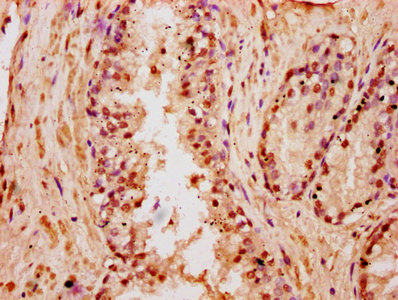

IHC image of CSB-PA010418OA18nbutHU diluted at 1:5 and staining in paraffin-embedded human pancreatic cancer performed on a Leica BondTM system. After dewaxing and hydration, antigen retrieval was mediated by high pressure in a citrate buffer (pH 6.0). Section was blocked with 10% normal goat serum 30min at RT. Then primary antibody (1% BSA) was incubated at 4°C overnight. The primary is detected by a biotinylated secondary antibody and visualized using an HRP conjugated SP system.

IHC image of CSB-PA010418OA18nbutHU diluted at 1:5 and staining in paraffin-embedded human prostate cancer performed on a Leica BondTM system. After dewaxing and hydration, antigen retrieval was mediated by high pressure in a citrate buffer (pH 6.0). Section was blocked with 10% normal goat serum 30min at RT. Then primary antibody (1% BSA) was incubated at 4°C overnight. The primary is detected by a biotinylated secondary antibody and visualized using an HRP conjugated SP system.